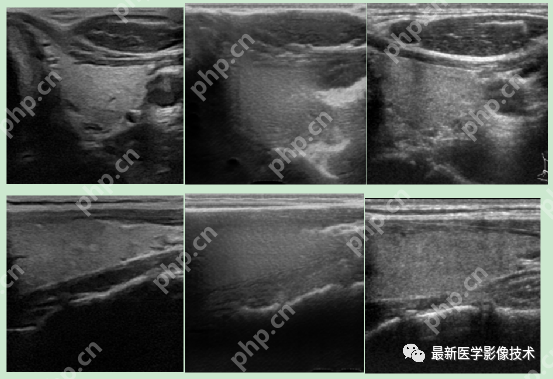

6、测试集部分生成结果

左图为低质量图像,右图为生成的高质量图像。